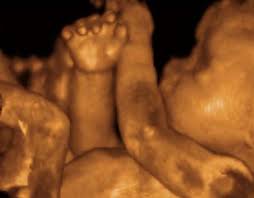

Imbasan 3D adalah gambar-gambar pegun bayi anda dalam tiga dimensi,seperti foto yang kita kadang-kadang lihat di akhbar dan majalah.Imbasan 4D (keadaan 4 dimensi) bergerak imej 3D bayi. Dengan imbasan 3D dan 4D, kita dapat lihat kulit bayi yang meliputi organ-organ dalaman. Kita dapat melihat bentuk mulut dan hidung bayi kita, lihat dia menguap atau melekat lidahnya, dan mendapat idea sama ada dia kelihatan lebih seperti ibu atau ayah.

Sesuatu teknologi itu akan pasti terdapat kelebihan dan kekuranganya juga. Salah satunya ialah kita dapat mengetahui sama ada kandungan kita itu normal atau abnormal. Gambar yang dipaparkan pulak tidaklah seperti kita tengok di televisyen tetapi hampir sama dengan apa yang kita tengok dengan teknik ultra sound, cuma bentuk badan itu sahaja yang dapat kita lihat dengan lebih terperinci.

Teknologi ini juga amat bagus untuk doktor melihat keadaan organ dalaman bayi seperti jantung, hati dan sebagainya. Andai terdapat masalah disitu, doktor akan terus dapat memberi diagnosis. Masa yang terbaik untuk melakukan scanning ini ialah pada minggu ke 26 atau minggu ke 30.